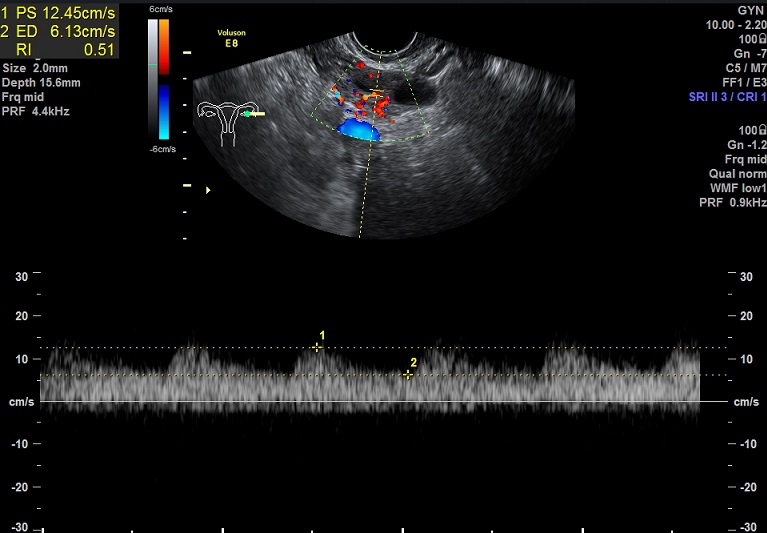

右卵巢: 大小3.3x2.0x1.1cm 体积:5.5 窦卵泡:5 卵巢间质血流:12.5cm/s RI:0.51